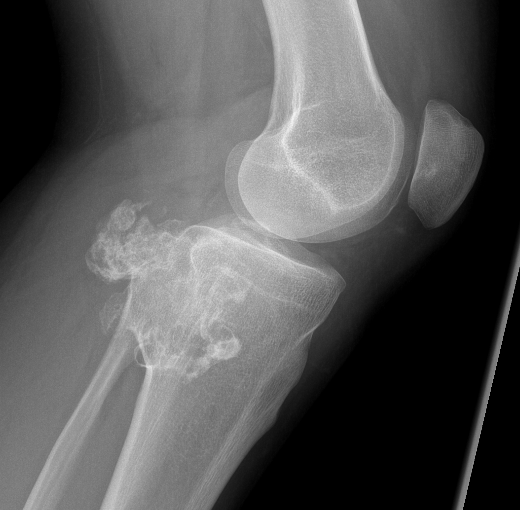

X-ray

Lytic lesion with punctate or spotty calcification

Worrisome features

- growth over time

- large > 5cm

- endosteal scalloping is hallmark of chondrosarcoma

Enchondroma enlarging over time